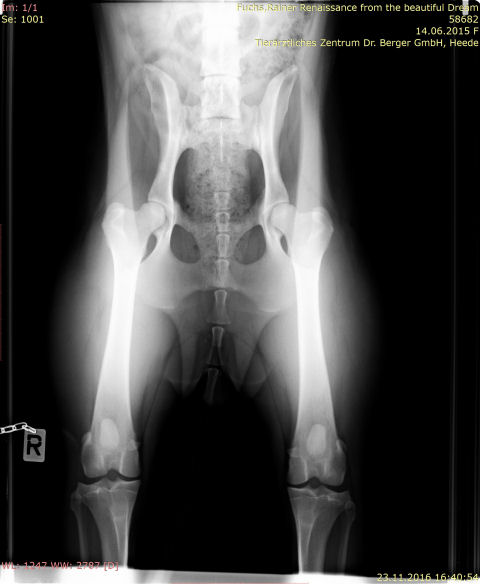

Roxy - HD-Röntgen

IMG-0003-00001-hüfte-roxy